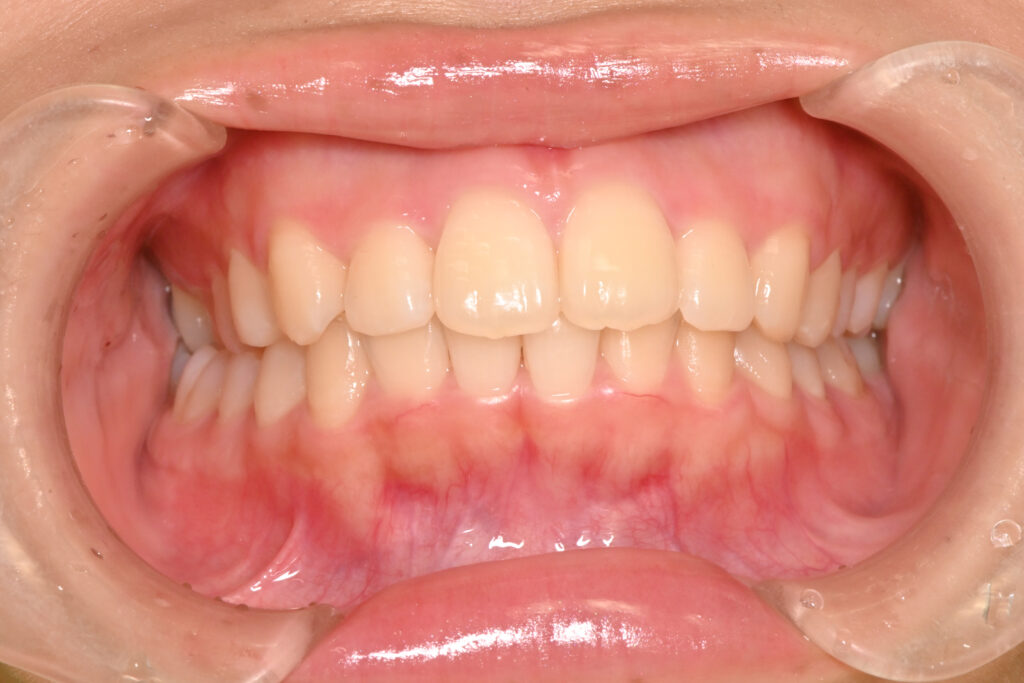

正面

治療後